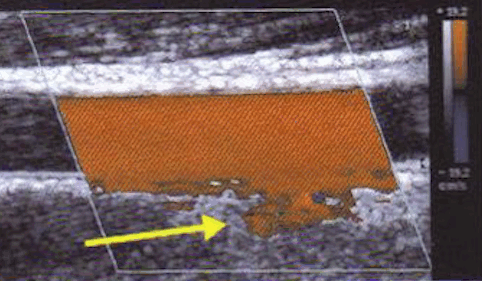

- Доплеровское картирование с контрастным усилением. Энергетическое допплеровское картирование (сolor amplitude imaging, CAI) показывает амплитуду доплеровского сигнала от движущегося кровотока, а цветное доплеровское картирование — средние сдвиги частоты доплеровского сигнала (т.е. среднюю скорость кровотока).

На рисунке опухоль молочной железы показана в режиме трехмерного энергетического допплеровского картирования до и после введения контрастного вещества. На усиленном 3D-изображении четко видна разветвленная внутриопухолевая сосудистая сеть (в двух плоскостях) и намного более крупные периферийные питающие сосуды. Это может означать, что для демонстрации хаотичной извилистости сосудов, связанных с неоваскуляризацией опухоли, 3D-режим подходит больше, чем 2D-режим.